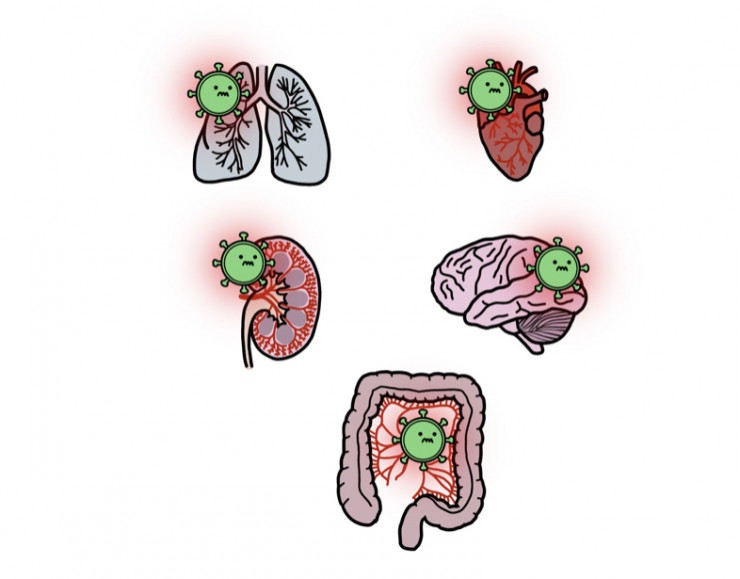

Коронавирус способен поражать любой человеческий орган, который кровоснабжается маленькими сосудами. Помимо легких, он поражает сердце, почки, головной мозг, кишечник. Кроме температуры и кашля появление любых симптомов должно настораживать и заставлять задумываться о возможности COVID-19.

Цитокиновый шторм наблюдается далеко не у всех пациентов с COVID-19, но если он развивается, то его следует ожидать на 10-е сутки после заражения. Большую опасность представляет дыхательная недостаточность, из-за которой иногда приходится идти на крайнюю меру – использовать аппарат искусственного дыхания – ИВЛ. Важно не доводить до этого. Также наблюдается воспаление сердечной мышцы, головного мозга, почек, поджелудочной железы и многих других органов.